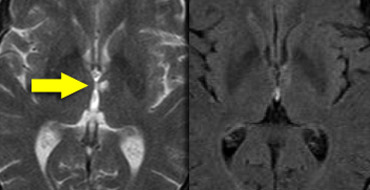

Bilateral medial strategic thalamus infarctions Bilateral medial strategic thalamus infarctions

The medial nuclei of the thalamus play an important role in memory and learning.

A large unilateral infarction or bilateral infarctions in this region can cause dementia.

You have to pay special attention to these areas to find these small infarctions.

FLAIR misses thalamus infarctions FLAIR misses thalamus infarctions

On FLAIR images you will easily miss these infarctions, because they can be isointense to the surrounding structures (8).

A high resolution T2WI is needed to detect these thalamic infarcts.

FLAIR in the infratentorial region and in the spinal cord is of limited value as it suppresses not only the signal of water, but also pathology with a long T1-relaxation time.